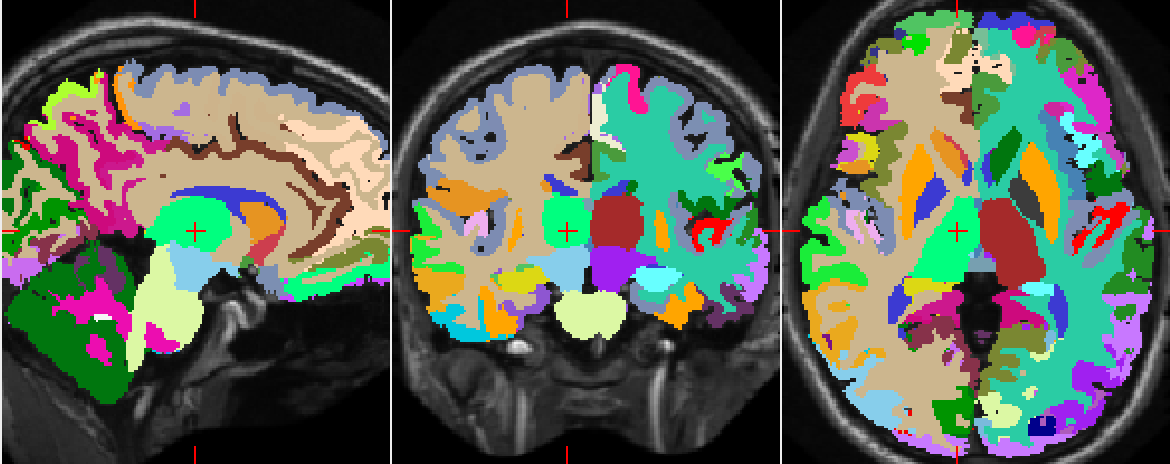

Refer to caption

(a) Manual segmentation.

(b) Predicted segmentation.

(c) Difference, white voxels are identical while blue are different.

Figure 7: Comparison of the manual brain segmentation of a subject (ID: 1004) to that predicted by SegNet. The mean dice coefficient is 0.74.

Figure 6 illustrates how well the downscaled patches and the distances to centroids enforce the global spatial consistency of the segmentations. Figure 7 shows the manual and automatic segmentations of a particular MRI. We notice that the misclassified voxels tend to lie on the boundaries of the regions, as expected.